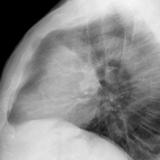

Case 8b Thymoma Lat

Date: 03/27/2009

Views: 14094